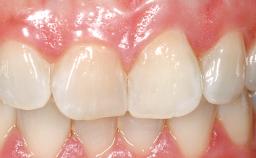

Late Placement of an Implant in a Maxillary Left Central Incisor Site

A 36-year-old female patient was referred for the replacement of the upper left central incisor (tooth 21), which had fractured. Although the tooth had been asymptomatic for many years, the crown began to loosen, at which time she presented to her dentist for an assessment. Teeth 21 and 22 had both been endodontically treated many years previously. She was a healthy individual and a non-smoker.

On examination, the patient had a low lip line and only displayed the coronal half of the anterior teeth when smiling.

Abutment Type Customized

Prosthesis Type FDP

Soft Tissue Contour and Volume Slightly compromised